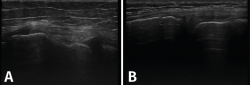

Figura 7. Corte coronal de una ecografía de rodilla. A: engrosamiento del ligamento lateral externo en la inserción proximal por un esguince de grado I; B: engrosamiento del ligamento lateral interno.

Tanto el ligamento lateral interno (LLI) como el ligamento lateral externo (LLE) pueden ser valorados por ecografía (Figura 7).